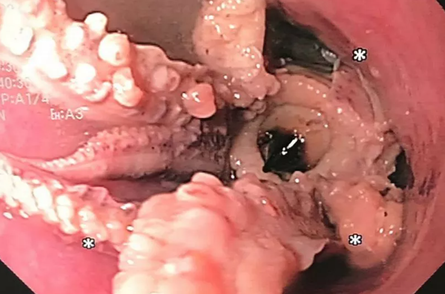

Комп'ютерна томографія виявила гіперщільну масу на відстані 5 см від стравохідно-шлункового з'єднання у пацієнта. Як з’ясувалося, там застряг восьминіг.

Перша спроба дістати восьминога з горла пацієнта не увінчалась успіхом. Тож довелось обережно ввести в шлунок ендоскоп, щоб схопити тваринку пінцетом за голову та витягнути. Процедура пройшла успішно, пацієнт швидко оговтався і його виписали вже через два дні.

Перша спроба дістати восьминога з горла пацієнта не увінчалась успіхом, тож довелось обережно ввести в шлунок ендоскоп